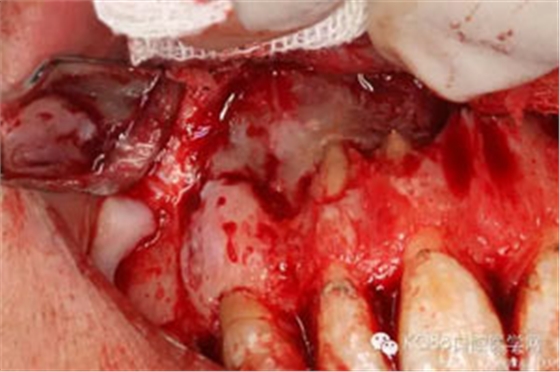

圖4.翻瓣、去除覆蓋在囊腫表面骨質(zhì),暴露出囊壁。

圖5.沿著骨壁完整剝離囊壁